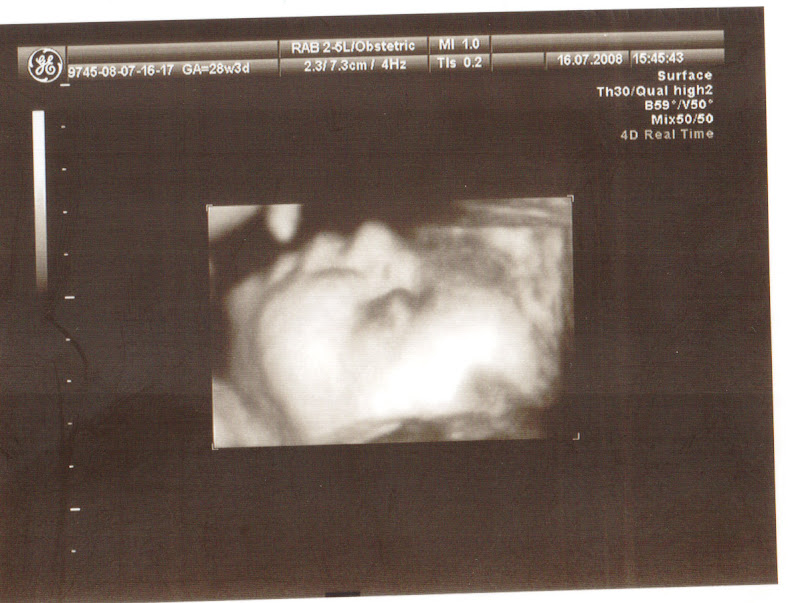

PS. A Zosia wygląda tak:

Na tym ujęciu Maciek się jej nie wyprze, policzki ma tatusiowe :)

A tu się nam Mała Ziaba usmiecha:

Bardzo długo się wahałam, czy umieszczać jej "zdjęcia" w sieci. Ale co tam - chcę się nią już pochwalić, o!! :)

PS. A Zosia wygląda tak:

Na tym ujęciu Maciek się jej nie wyprze, policzki ma tatusiowe :)

A tu się nam Mała Ziaba usmiecha:

Bardzo długo się wahałam, czy umieszczać jej "zdjęcia" w sieci. Ale co tam - chcę się nią już pochwalić, o!! :)